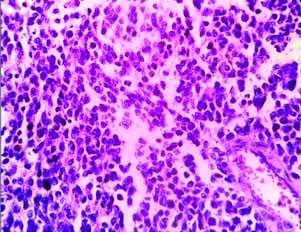

Microscopy showed breast parenchyma with a neoplasm arranged in sheets, lobules, nests and alveolar pattern [Table/Fig-2,3]. The tumour cells are small round with scant cytoplasm, round vesicular nucleus separated by fibrous septa seen infiltrating into the adjacent fatty tissue [Table/Fig-2,3]. Stroma showed lymphocytic infiltrate. The NAC, superior, inferior margin showed tumour infiltration. Rest of the margins and posterior margin were free. Five out of 11 nodes showed metastatic deposits with similar morphology [Table/Fig-4]. With this histology, we came to the conclusion of possibilities of small round cell tumour of breast.

Tumour cells are small round with scant cytoplasm with vesicular nucleus (H&E, 40x view).